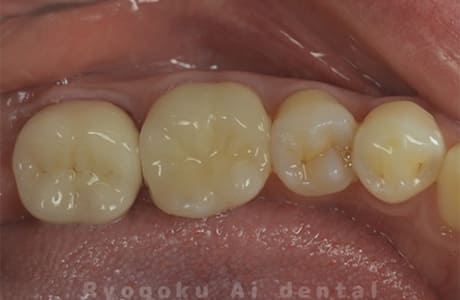

Case16

-

- 原因

- 重度カリエス

- 治療内容

- マイクロエンド

- 治療費用

- 77,000円(被せ物の費用は別途)

- 担当医

- Dr. 炭野

歯が欠けたとのことでご来院された患者様です。神経まで虫歯が及んでいたため、神経を除去し、治療を行いました。経過良好です。